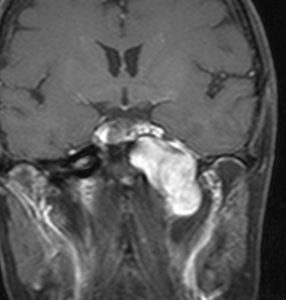

典型的な例1

舌萎縮(舌が右側に曲がっている)に気づいて発見された舌下神経鞘腫です。

舌の右側だけが痩せて萎縮しています,前に出すと麻痺側に曲がります。

舌に波のようなシワができます。

頭蓋底の舌下神経管から頭蓋底部,深頸部に伸びた6cmくらいある大きな舌下神経鞘腫です。舌萎縮以外の症状がないので,手術しないで何年も経過観察していますが大きさは変わりません。右側の画像では内頸動脈が圧迫されていますが,狭窄して血流が悪くなるようなことはありません。